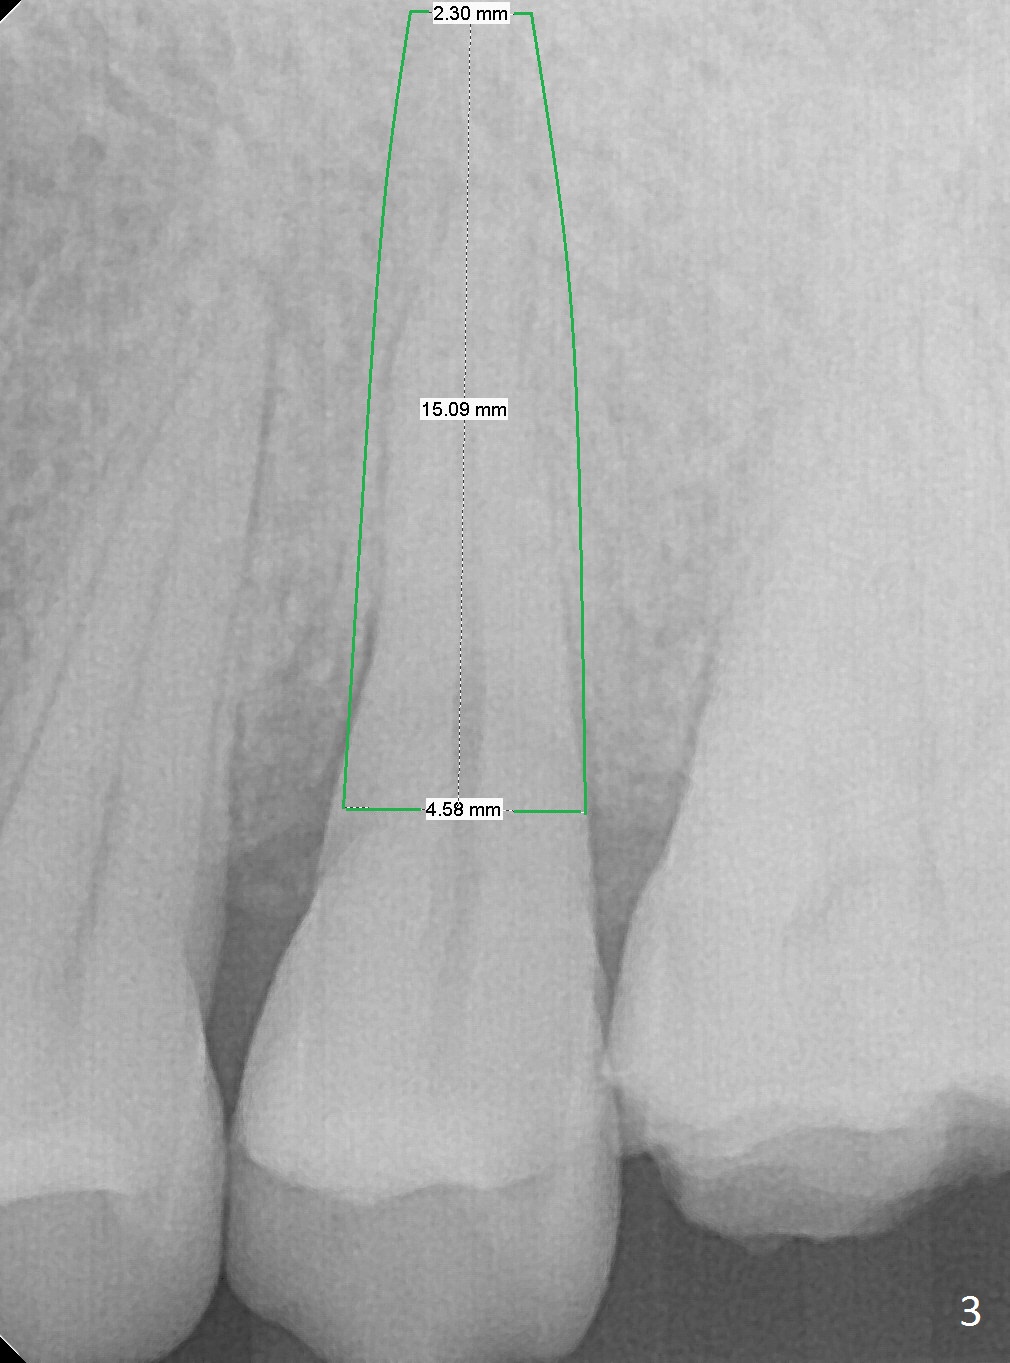

3.8 or 4.0x15 mm Implant

A 42-year-old woman presents to clinic with cc "top left tooth cracks upon biting on a small piece of stone". The buccal gingiva is tender, corresponding to the loose buccal segment of the tooth #13 (Fig.1). The crack may be secondary to severe wear of the 1st molar (Fig.1,2) in addition to deep slope of the affected tooth. A 4.5x15 mm IBS implant will be placed (Fig.3). Take PA following pilot drilling.